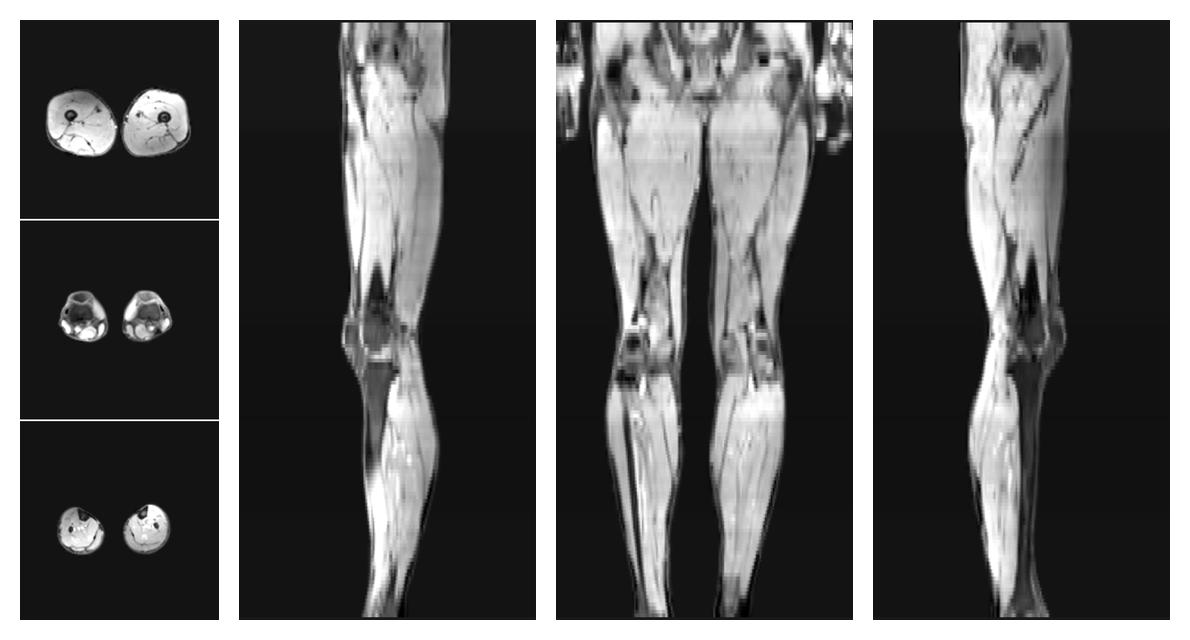

• Water only signal

The water part of the acquired multi-echo spin echo data.